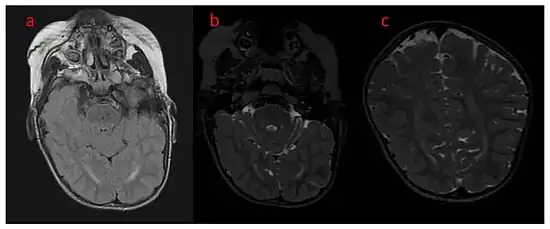

While initial diagnosis is based mostly on clinical suspicion, definitive diagnosis requires confirmation by genetic testing. The first presentation of epileptic seizures within the first few months of life would suggest a possible diagnosis of CDD. Initial clinical testing for differential diagnosis may include MRI and CSF testing for structural or infectious etiologies; however, CDKL5 is now widely included in DNA sequence-based molecular diagnostic gene panels or infantile epilepsy for more rapid and precise diagnosis. Note: many adolescents and young adults may have CDD but were never tested since such tests were not available when they were infants. Therefore, epilepsy panels for CDD and other genes should be considered in such individuals.[8]